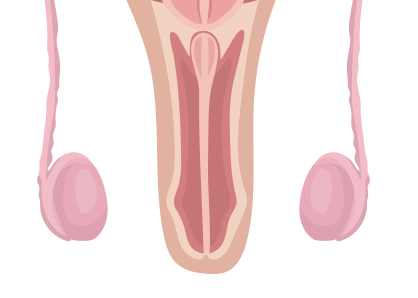

고환은 정자와 테스토스테론을 생성하는 중요 기관입니다. 고환/부고환염, 고환염전, 정계정맥류, 음낭수종 등 고환에 발생할 수 있는 다양한 질환을 적절한 방법으로 치료해야 합니다.

고환이나 부고환의 외상이나 요도로부터 소변이 역류가 되어 발생하기도 하지만 대부분의 경우 요로 감염에 의해 발생하게 됩니다. 세균이 요도나 전립선에 존재하다가 소변의 압력에 의해 고환이나 부고환에 도달하게 되어 염증을 일으키게 됩니다.

심한 통증이 갑자이 음낭 내에서 발생하게 되고 심할 경우 하복부 통증이 동반되기도 합니다.

고환으로 들어가는 정삭의 꼬임으로 고환으로 혈액 공급이 차단되어 고환의 통증을 유발하는 질환으로 주로 사춘기 남아에게서 많이 발생합니다.

사춘기에 고환의 성장이 진행되면서 정삭을 둘러싸고 있는 근육의 수축으로 발생할 수 있으며 극심한 고환통과 구역질, 구토가 동반될 수 있습니다.

음낭 내에 있는 정맥의 혈관이 확장되어 음낭에 울퉁불퉁한 모습으로 확장된 혈관이 관찰되는 질환입니다.

배변을 할 때 아랫배에 힘을 주게 되면 겨우 만져지는 경미한 정계정맥류가 있을 수 있고, 심할 경우 음낭에 벌레가 기어다니는 듯한 확장된 혈관이 관찰될 수 있습니다.

고환 주위에 물이 차는 지로한으로 고환을 둘러싸고 있는 초막에 액체가 고이는 질환입니다. 액체가 점차 부풀어오르기 때문에 방치하면 커다란 종물로 만져질 수 있습니다.

소아의 경우 고환을 둘러싸고 있는 초막이 복강과 연결되어 있어서 복강 내 복수가 음낭내로 내려와 발생할 수 있으며, 성인의 경우 초막 내에 정상적으로 존재하는 고환수에 대한 분비과 흡수 사이의 불균형에 의해 발생합니다.